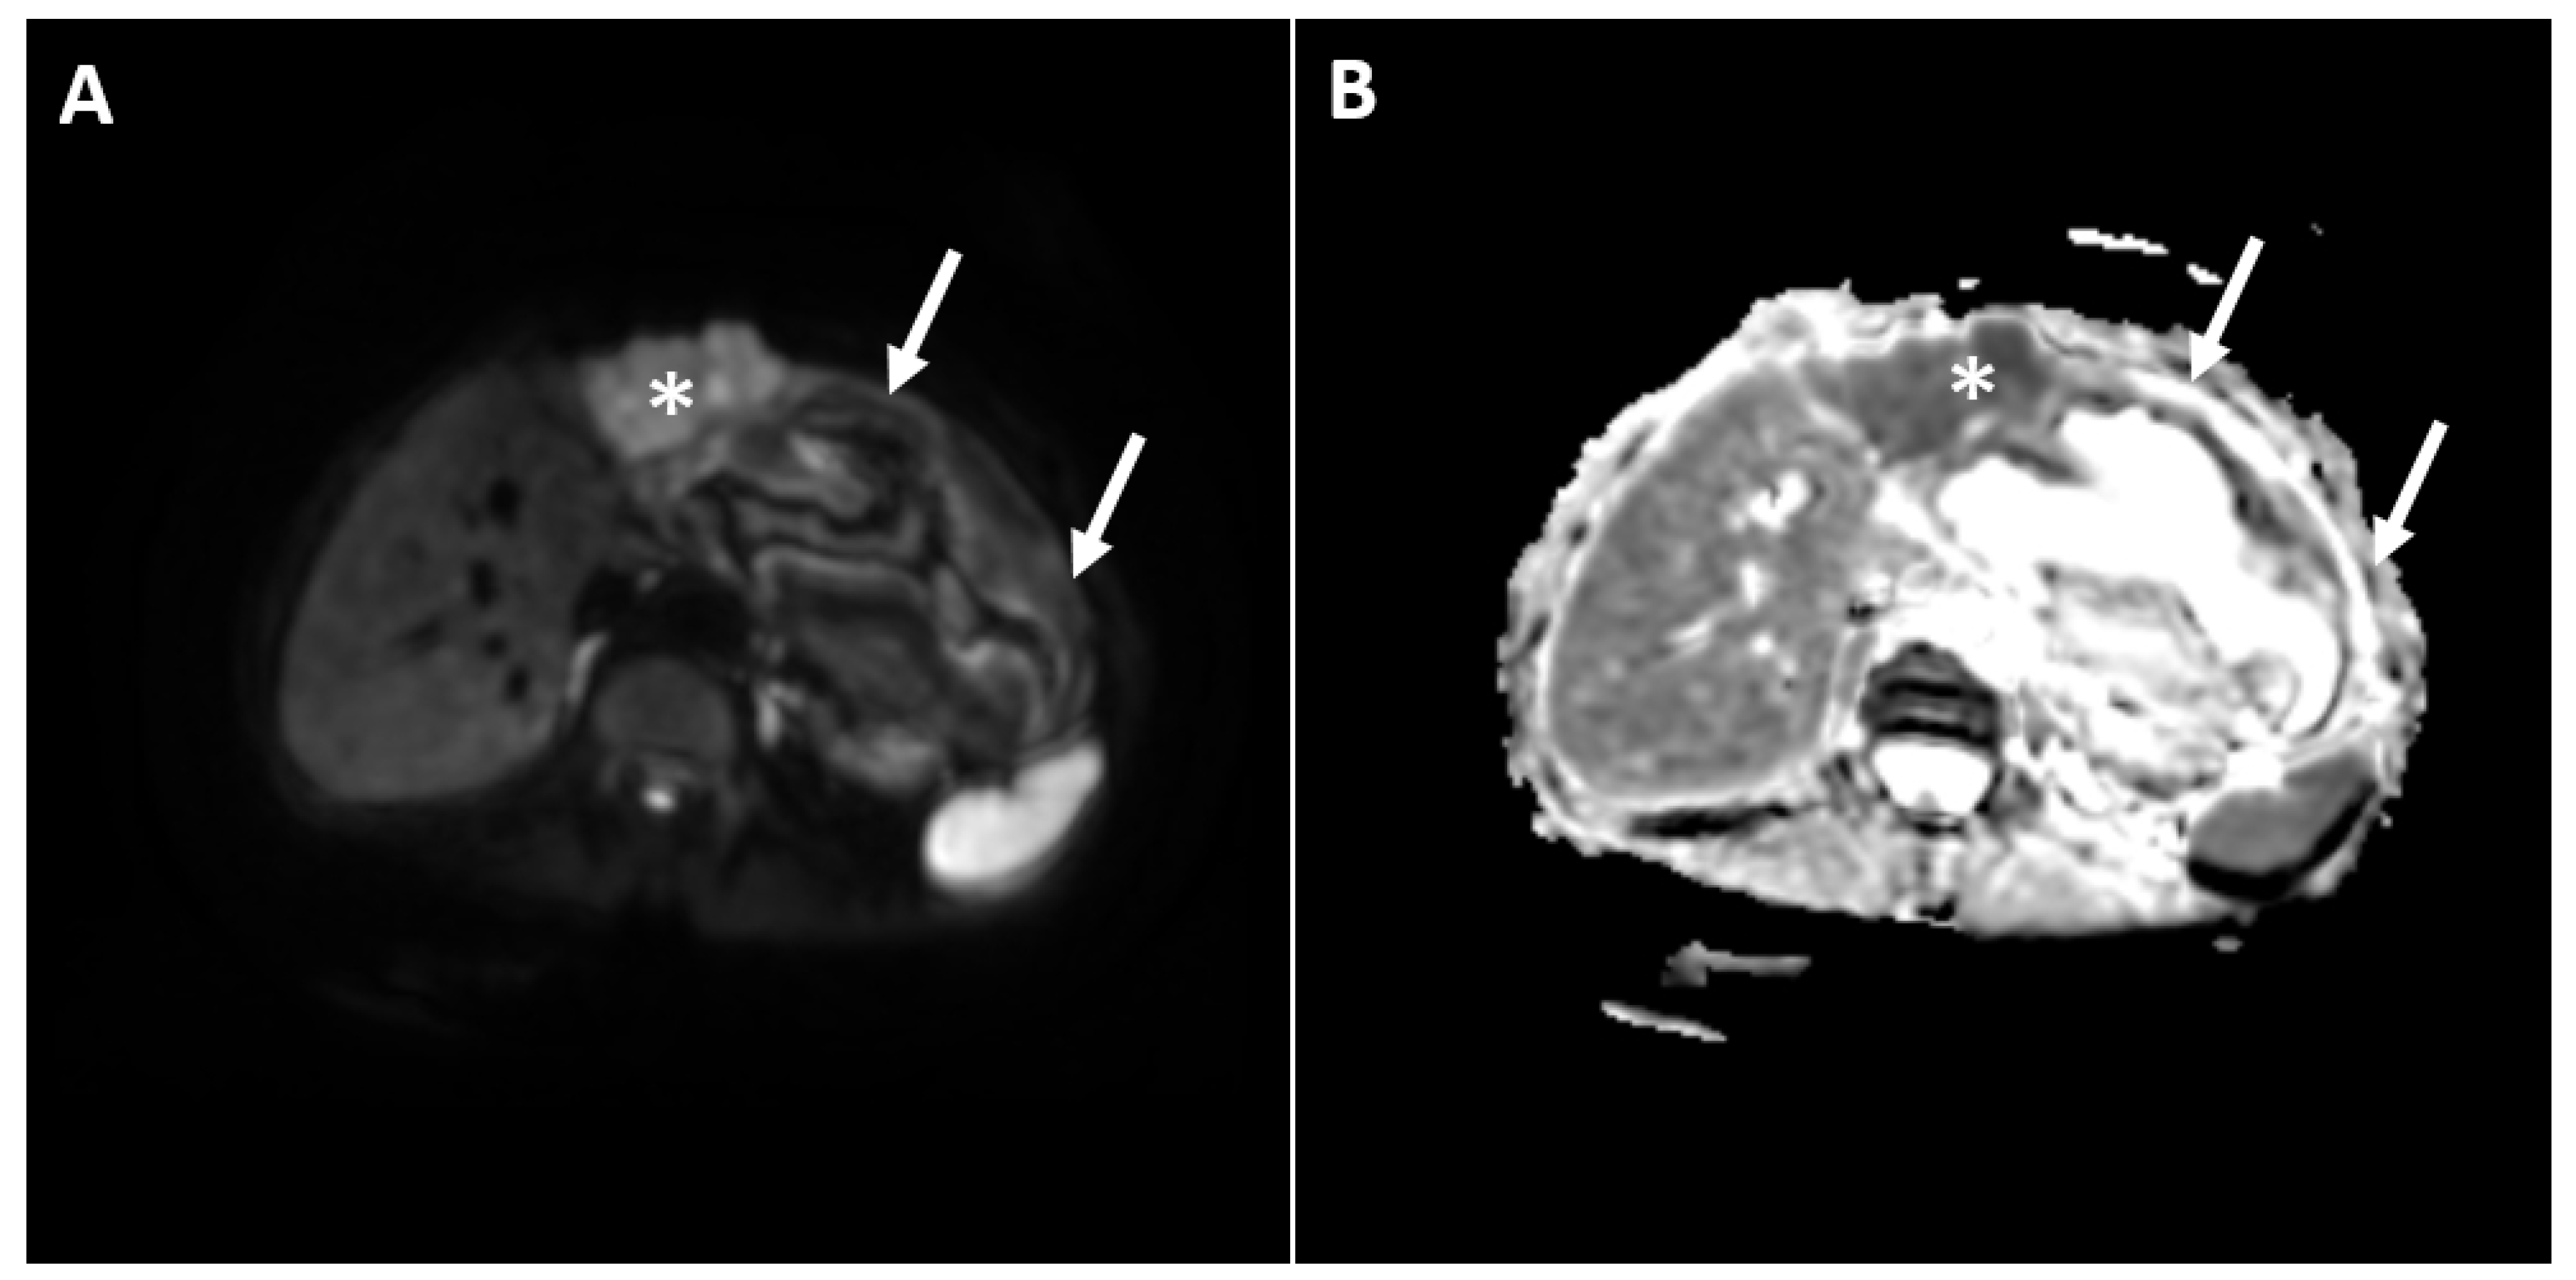

2. Case Report